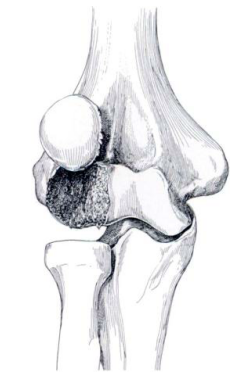

<br />Только перелом головки (головчатого возвышения, capitulum) плечевой кости 1 типа.<br /><br />Hahn лечил 63 летнюю женщину с травмой локтевого сустава 3-х летней давности и впервые в мировой литературе описал эту травму в 1853 году. К сожалению, результат лечения был неудовлетворительный.<br /><br />В последующие годы была предложена классификация переломов головки плечевой кости, в которой было выделено 4 типа:<br /><br />1 тип (Hahn-Steinthal type) представляет собой, т. наз. "полный перелом", при котором головка типично смещается кпереди и вверх. Плоскость излома лежит во фронтальной плоскости, а костный фрагмент по сути представляет свободное тело в полости сустава.<br /><br />

<br /><br />3 тип (Broberg и Morrey) - оскольчатый перелом головки плечевой кости.<br /><br />4 тип McKee - перелом головки плечевой кости с переходом линии излома на блок.<br /><br />